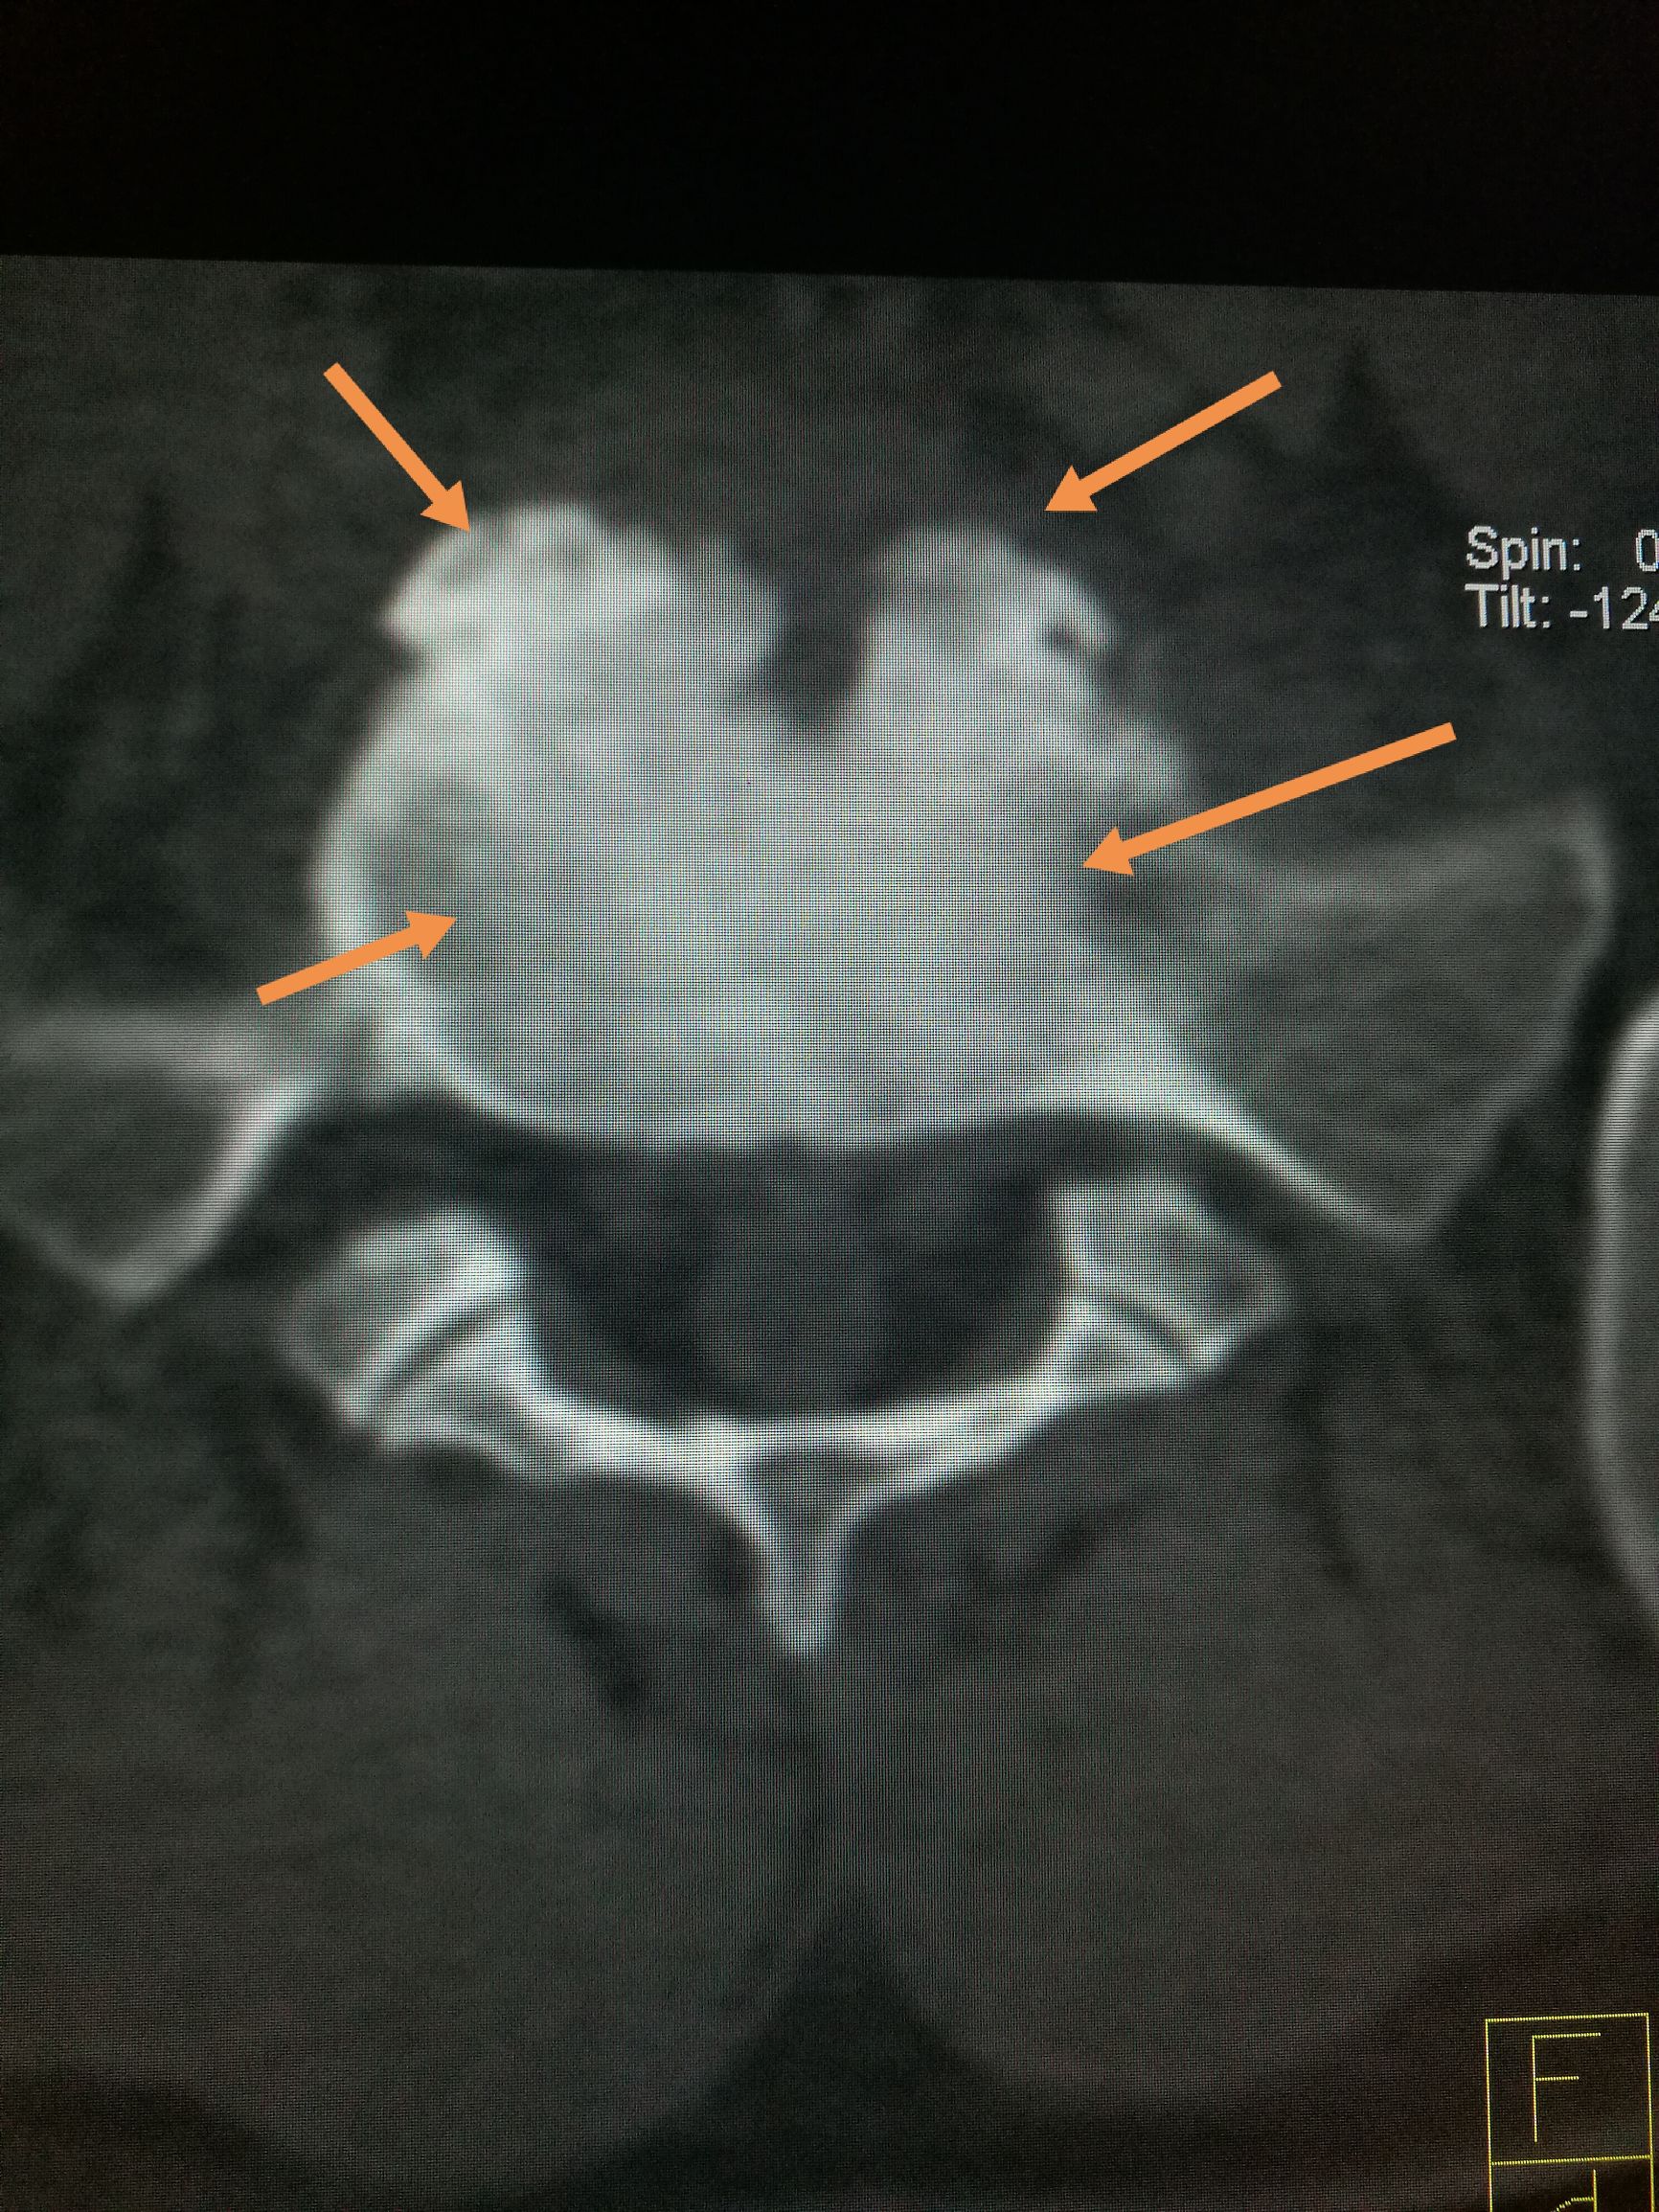

吃羊肉腰胀疼是怎么了,经常吃牛羊肉身体有啥变化 ​​​患者,男,22岁,以腰疼数月前来我处就诊,CT扫描可见第五腰椎下缘,骶椎上缘骨质破坏,骨密度增高,椎间隙未见明显狭窄,椎体旁未见软组织肿胀,未见异常包块,随后追问病史,主诉在*疆新**生活两年,后腰疼,在省防疫站查出来是布鲁氏杆菌感染,今来我处复查。